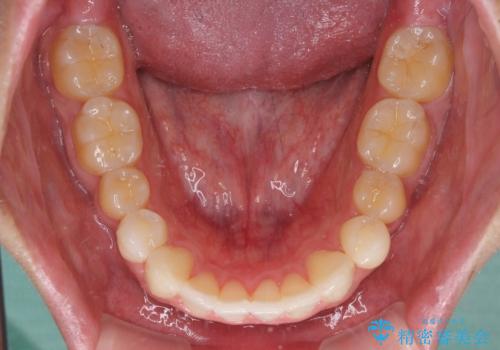

八重歯と奥歯のクロスバイト 上顎骨を拡大してインビザラインで矯正

- 八重歯を気にして来院された患者様です。

八重歯が著しいため、抜歯矯正も視野に入れて検討しましたが、臼歯の咬合関係は正常に近かったので、非抜歯矯正で進める方針としました。

上顎骨の幅が狭く、奥歯がクロスバイトとなっていたため、急速拡大装置を用いて上顎骨を側方拡大し、八重歯を収めるスペースを獲得しつつクロスバイトを改善することとしました。